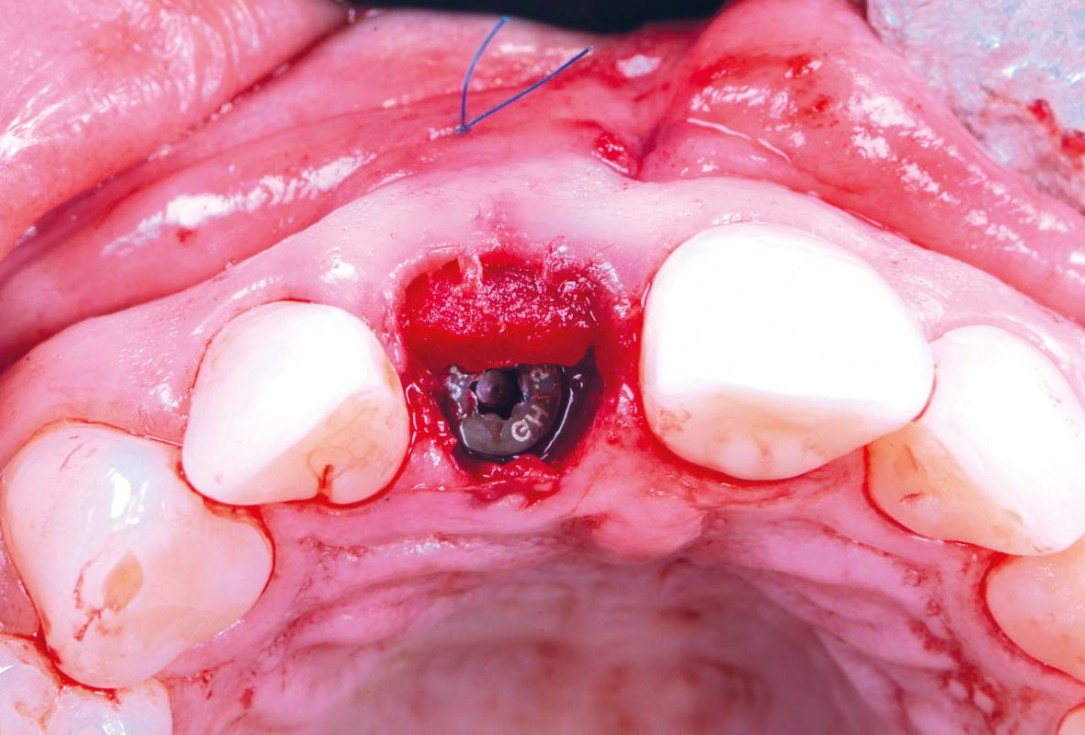

Immediate implant placement using cerabone® and collagen fleece - Dr. D. Jelušić

Pre-operative situation showing tooth 21 with deep periodontal pocket. Tooth presented with mobility grade III.